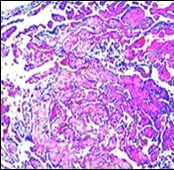

On microscopy, superficial squamous epithelial surface is intact. Sub-epithelial connective tissue stroma exhibits slit-like, vascular spaces. Upon extended magnification, multiple, intravascular papillary projections encompassed within a hyalinised stroma are discerned. Centroidal calcification appears in combination with intravascular, papillary endothelial cell proliferation, lined with singular layer of endothelial cells devoid of cytological atypia6, 7.

Characteristically, the vascular neoplasm denominates numerous papillae within blood vessels. Papillae are coated with singular or dual layer of flattened endothelial cells with an encompassing hyalinised, fibrous tissue core. Vascular lumen is distended with thrombosis. Foci of haemorrhage with fibrinous and purulent exudate are discerned. Tumour perimeter depicts inflammatory granulation tissue. Cholesterol clefts and focal reactive bone formation may concur. Extraneous squamous epithelium may be discontinuous and ulcerated. The neoplasm is devoid of features of malignancy4, 6.

Numerous micro-calcifications can be observed within the lesion which may engender vascular occlusion and tissue necrosis6. Figure 1, Figure 2, Figure 3, Figure 4, Figure 5, Figure 6, Figure 7, Figure 8.

Figure 1 Papillary endothelial hyperplasia elucidating papillary articulations layered with a single layer of endothelial cells and a commingling of fibrinous, thrombotic exudate 10.